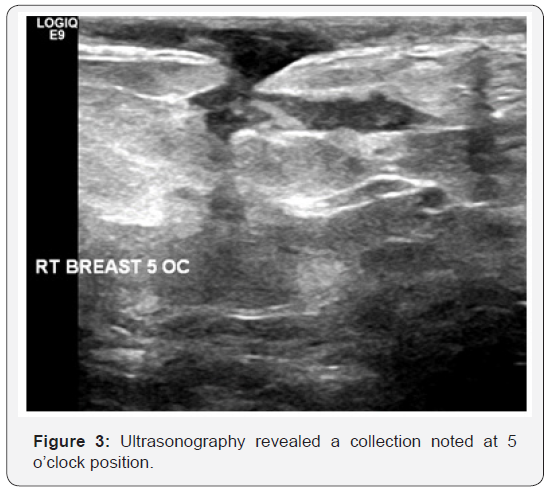

33 year-old female presented herself with pain right breast and history of TB. On clinical examination, the patient had two masses in right breast. The patient was initially examined with mammography which showed asymmetric density at right lower inner quadrant. No pleomorphic microcalcification, architectural distortion or obvious masses (Figure 1 & 2). The routine complementary breast ultrasound was done with a high frequency (8-10MHz) linear array head, which showed two collections noted at 5 and 8-9 o’clock positions (Figure 3 & 4). Finally US-guided fine needle aspiration was done. Also pathological, bacteriological analysis, and polymerase chain reaction (PCR) were done to prove the tuberculous nature of their lesions.

In our case ultrasonography finding are multiple collections and this agree with Adeiza et al. [6] stated that say lesions due to TB have no specific ultrasonographic findings. They may be heterogeneous, hypoechoic, irregularly bordered mass with internal echoes or thickwalled cystic lesions on ultrasonography. In some cases, there may be fistula formation and thickening of Cooper’s ligaments and subcutaneous tissues [6]. MRI may be used in select cases when the sonographic or CT findings are inconclusive. CT may be skipped and an MRI study may be directly performed, especially if the breast abnormality is first detected on ultrasound, to save the patient from radiation exposure. MRI is more successful for delineating the internal structure of breast TB lesions, and the central liquefaction or abscess might be easier to detect, which may potentially affect the decision for treatment approach [5].